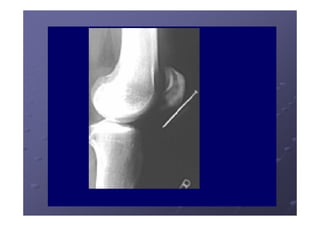

Opacidades Básicas

Fundamentos da Radiologia (Propriedades dos Raios X) São capazes de atravessar corpos opacos. Produzem radiações secundárias nos corpos atravessados. Durante a travessia sofrem atenuação dependente da espessura e densidade do corpo considerado.